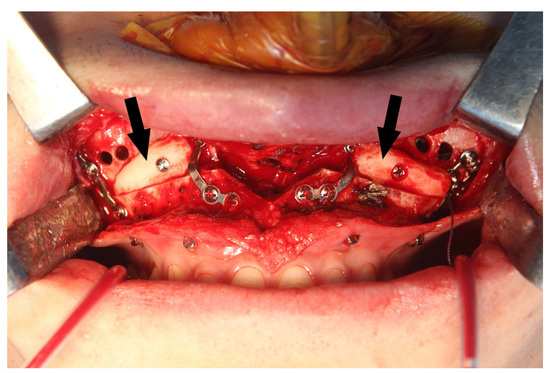

Questions may arise as to whether the bony holes drilled to apply the MSVD will heal completely with time. We observed that drilled bony holes had become smaller during the metal removal surgery at 2 years after bimaxillary orthognathic surgery (Figure 7). These remaining bony defects did not clinically affect the physiology or function of the maxillary sinus. At the last follow up, 4 years after the procedure, there were no other sino-nasal clinical symptoms or complications regarding the MSVD. All tubes should be removed the day after operation to prevent the active post-operative bleeding. According to our experience, there was no case of late bleeding in the group of patients with MSVD. However, it is important to alertly monitor for late bleeding.

Figure 7.

The drilled bony holes for the maxillary sinus ventilation drainage had become smaller (arrows) at 2 years after the bimaxillary orthognathic surgery.